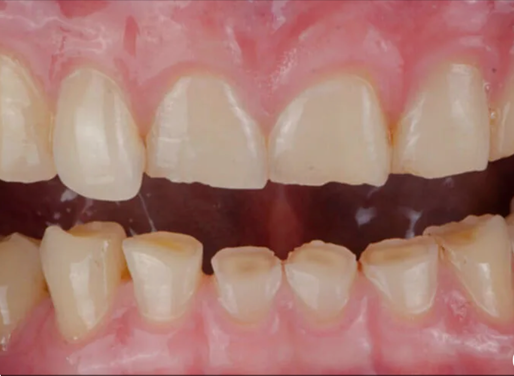

3. Los problemas de mordida empeoran con el tiempo

En niños y adolescentes, una evaluación temprana permite guiar el crecimiento y evitar tratamientos más invasivos en la adultez. En adultos, la progresión puede generar desgaste, movilidad o sobrecarga articular.

Fig.3 Maloclusión en niños y en adultos